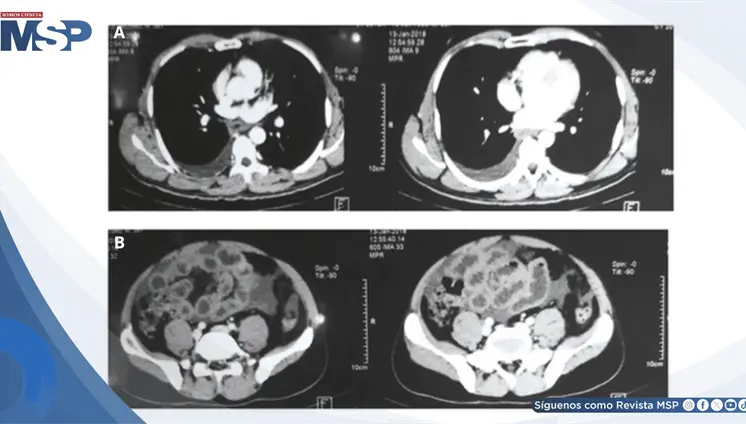

Las lesiones óseas osteolíticas, anemia y alteraciones hematológicas h...

Aunque incurable, esta neoplasia de células plasmáticas ya se controla de forma crónica gracias a innovaciones como anticuerpos monoclonales y terapias CAR-T, accesibles en Puerto Rico

Especialista explica qué es esta malignidad de células plasmáticas, cómo se detecta y por qué los avances en tratamientos han transformado radicalmente el pronóstico de los pacientes.